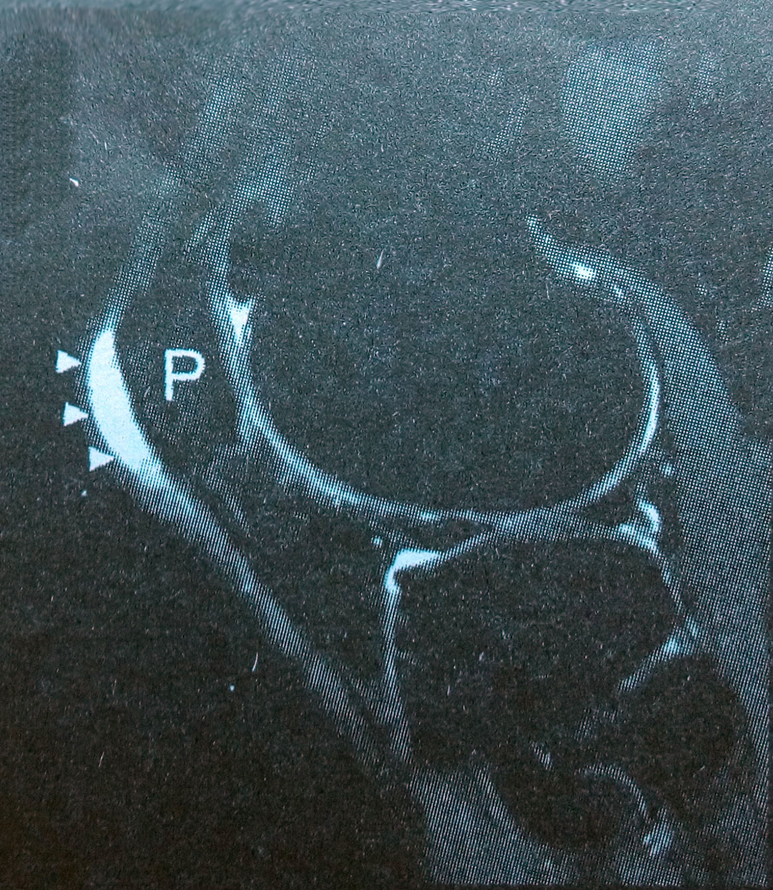

MRI表现:

• 腘窝囊肿在膝关节MRI检查中出现率为10-41%,而且出现率随年龄增长、关节炎或关节积液的出现而升高。

• 早期无症状,体检偶尔发现;

• 腘窝囊肿常位于腓肠肌内侧头与半膜肌之间,呈圆形、卵圆形外观,有时能见到一 “细颈”与关节腔相通,“细颈”的出现是腘窝囊肿特征性影像表现;

• 腘窝囊肿在T1WI上为均匀低信号,T2WI上呈均匀高信号,STIR压脂表现为均匀高信号;

• 当囊内出血时可因出血量的多少和时间长短而出现不同信号改变;

• 继发感染时囊壁增厚,行Gd-DTPA增强增厚的囊壁有中等样强化。